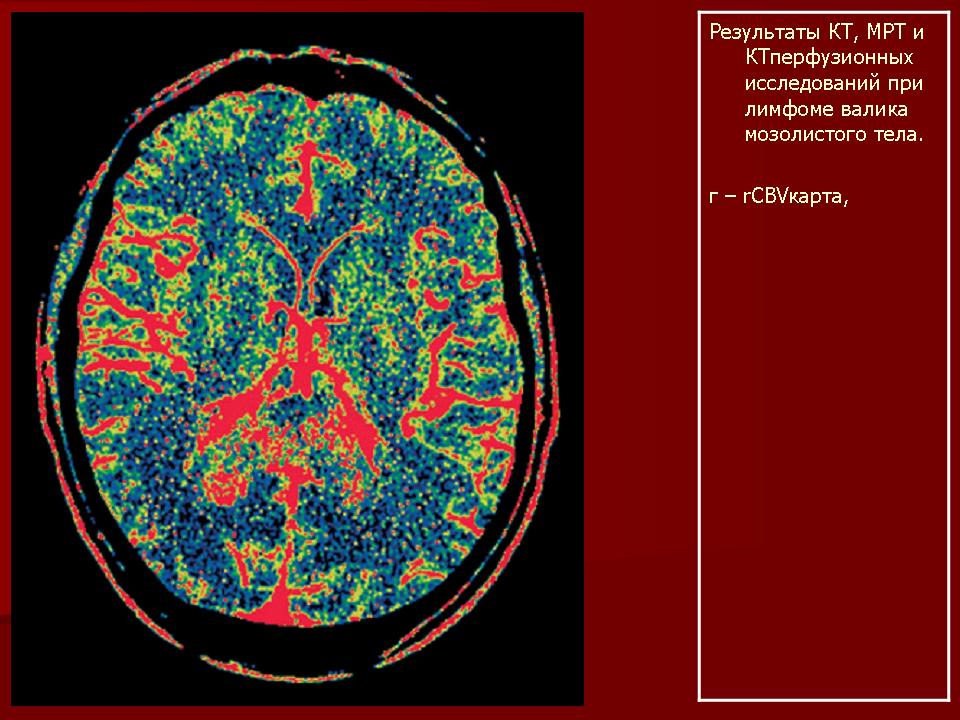

Лимфомы головного мозга.

1.Uv_.Slayd48.JPG2.Uv_.Slayd49.JPG3.Uv_.Slayd50.JPG4.Uv_.Slayd51.JPG5.Uv_.Slayd52.JPG6.Uv_.Slayd53.JPG7.Uv_.Slayd54.JPG8.Uv_.Slayd55.JPG9.Uv_.Slayd56.JPG10._Uv.Slayd57.JPG11.Uv_.Slayd58.JPG